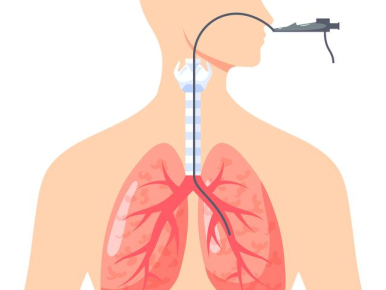

支气管镜是一种细长的、柔软的、可弯曲的管状仪器,它通过鼻腔或口腔插入,经过咽喉、气管,最终到达支气管。支气管镜上配备有光源和摄像头,能够将呼吸道内部的影像实时传输到显示屏上,让医生清晰地观察气管和支气管的管壁、管腔以及周围组织的情况。

支气管镜检查是呼吸系统疾病最重要的诊疗手段。对于慢性咳嗽、痰中带血、肺癌、肺结核、肺炎等诊疗评估,阻塞性肺炎、异物吸入、肺不张等疾病是首选诊疗措施。